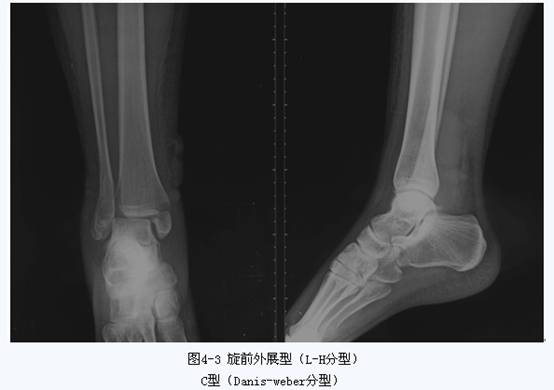

踝关节由胫腓骨下端与距骨组成。其骨折、脱位是骨科常见的损伤,多由间接暴力引起踝部扭伤后发生。根据暴力方向、大小及受伤时足的位置的不同可引起各种不同类型的骨折。目前临床常用分类方法是Lange-Hansen分类法、Davis-Weber分类法和AO分类法。Lange-Hansen分类法于1950年提出,根据足在受伤时的位置和暴力的方向将骨折分为旋后/内收型、旋后/外旋型、旋前/外展型和旋前/外旋型四类,每一类又根据骨折程度及是否伴有韧带软组织损伤而分为不同的亚类。该分类对于踝关节不稳定骨折的闭合复位有指导意义。Davis-Weber分类法根据外踝骨折的位置,把踝关节骨折分为A、B、C三型,该分类以下胫腓联合为界将骨折分为下胫腓联合水平以下的损伤(A型)、经下胫腓联合的腓骨骨折(B型)以及下胫腓联合以上损伤(C型),较简单,使用方便,但却不能说明整个踝关节各种复杂改变。国际创伤学会(AO)进一步细化了Davis-Weber分类法,提出了AO分类法。